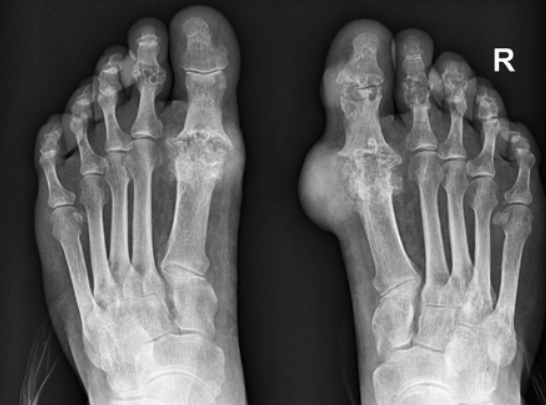

통풍 증상 두 번째는 엄지발가락 통증입니다. 처음에 주로 엄지발가락 근저부 관절에 발병하는데 돌발적인 통증과 함께 붉게 부어오르며 무릎, 손목, 발목, 팔꿈치 등에 발생하기도 합니다.

통풍 증상 네 번째는 급성 통풍 발작인데 엄지발가락, 발목 등 한 곳의 관절이 갑자기 빨갛게 부어오르고 손댈 수 없을 정도로 통증이 심한데 발뒤꿈치, 팔목, 손가락, 귀 등에서 나타나며 급성 통풍성 관절염이라고 부르기도 합니다.